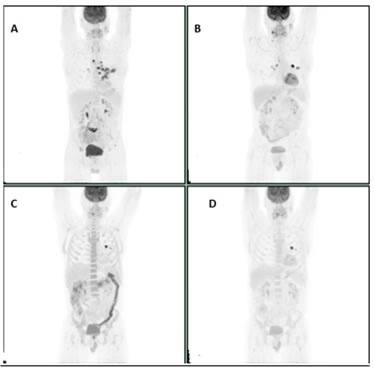

A 60-year-old woman who was initially diagnosed with oligometastatic non-small cell lung cancer (NSCLC) (EGFR and ALK-negative) in 2010. Biopsy confirmed mucinous adenocarcinoma. Initial PET scan showed metastatic lung adenocarcinoma. The patient was started on Carboplatin, Pemetrexed, and Bevacizumab for four cycles and later maintained on Pemetrexed and Bevacizumab. Given issues with tolerance, stable findings on imaging, patient was given chemo holiday from July2011 to December 2011. Computerized tomography (CT) scan done in December 2012 showed disease progression and single agent Pemetrexed was restarted. Restaging scans in March 2012 showed disease progression and was started on Docetaxel. Patient received Docetaxel till August 2012 and was later held due to stable disease on imaging. Reimaging in April 2014 showed complete resolution of the adrenal lesion. Patient received definitive radiation therapy to the lung lesion. Unfortunately, patient had recurrence with isolated adrenal lesion on PET scan done in October 2014 for which she underwent adrenalectomy and the pathology from this was consistent with metastatic mucinous adenocarcinoma with negative margins. Patient developed new cerebellar lesion in July 2015 which was resected. Imaging done in January 2016 demonstrated a new right adrenal lesion, and subsequently the patient was started on Nivolumab. The patient had an excellent response to Nivolumab but eventually progressed in November 2016 for which he was started on Docetaxel and received it from December 2016 to February 2017. PET /CT scan done in February 2017 showed resolution of all FDG avid lesions (Figure 4A-4D). Patient currently is under observation and remains in remission.

Figure 4: A: Initial study. B: Mild progression of the right adrenal lesion on Nivolumab. C: PET scan showing progression of right adrenal lesion further. Docetaxel started after this EPT scan. D: Resolution of the right adrenal lesion on PET scan.